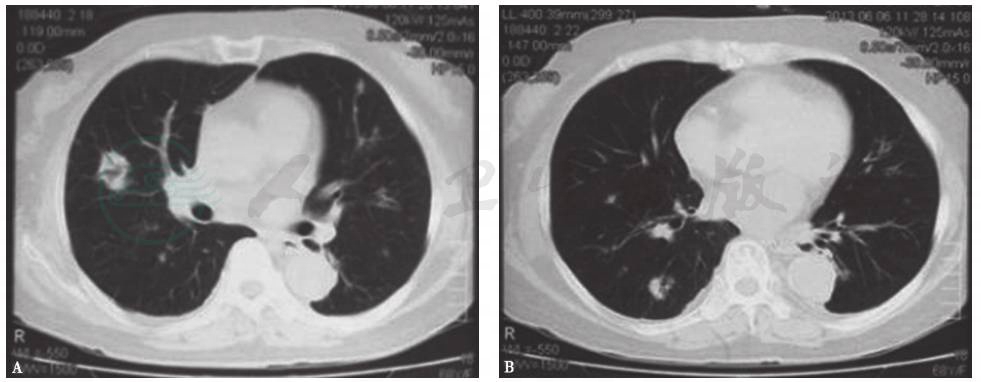

胸部CT:两肺见散在多个片状、花环状高密度影,反晕征,部分密度不均,边缘尚清,部分相互融合,大部分可见含气支气管征(图7)。

图7 入院后胸部CT表现(发病第50天)

患者入院后所做系列检查显示:①肿瘤标志物及大便检查均阴性,结合临床表现,基本上可排除胃肠道肿瘤肺转移;②虽然抗核抗体为1∶100,但其余自身抗体均阴性,结合临床表现,暂不考虑风湿免疫病;③胸部CT提示病变进一步加重;④常规病原学检查均阴性。因此,不排除曲霉菌感染的可能。但患者应用伊曲康唑治疗10天后,复查胸部CT(图8)提示病情进一步加重,且静息状态下动脉血气呈现低氧血症(FiO2 33%,PaO2 64mmHg)。由此推测,本病例可能是由一些非感染非肿瘤性疾病引起。

图8 入院后胸部CT表现(发病第58天)

胸部CT显示,与发病第50天时(图7)相比,双肺原有病灶进一步加重,并出现右侧少量胸腔积液